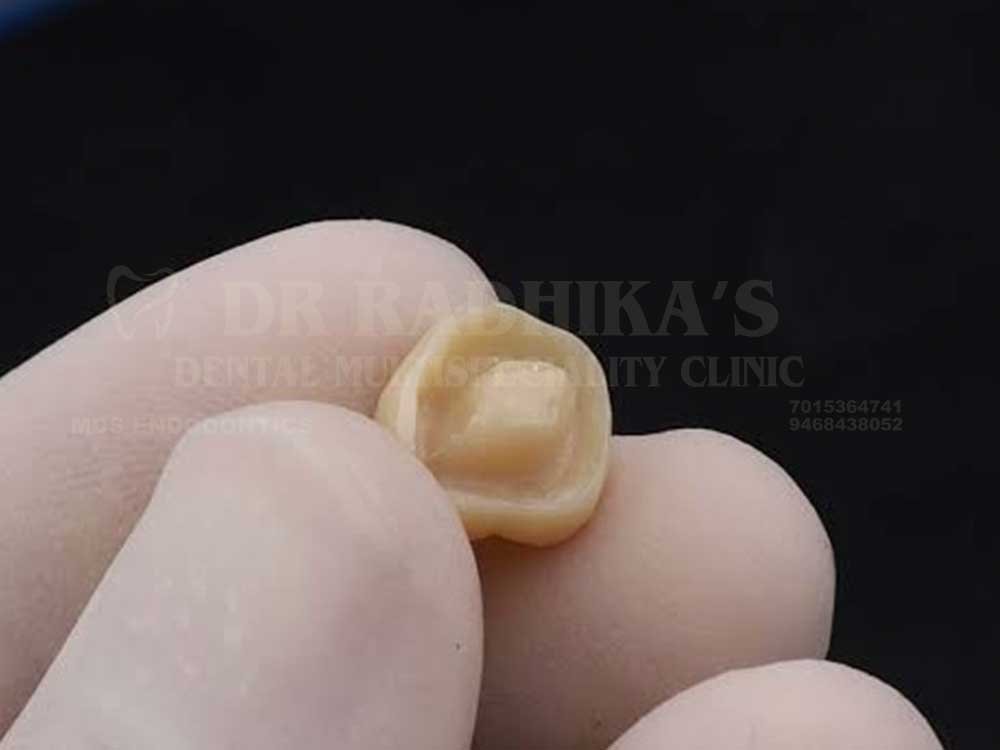

Endo crowns are tooth-coloured restorations designed for root canal–treated teeth. They bond directly to the tooth structure, providing strength, durability, and a natural look.

Endo Crowns are advanced tooth-coloured restorations specially designed for teeth that have undergone root canal treatment. Made from strong ceramic or resin-based materials, they bond directly to the remaining tooth structure, ensuring durability and a natural look. Unlike traditional crowns, Endo Crowns are more conservative, requiring less removal of healthy tooth structure.

Natural Appearance: Made from tooth-coloured ceramic or resin, they blend seamlessly with your natural teeth.

Conservative Approach: Require less removal of healthy tooth compared to traditional crowns.